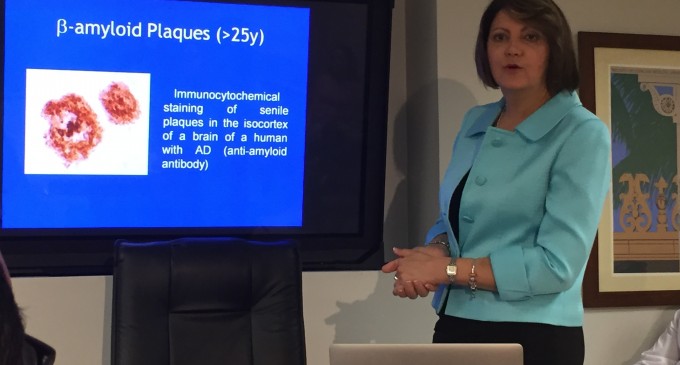

La ginecóloga oncóloga puertorriqueña Teresa Díaz Montes está al mando del primer estudio que se realiza en Estados Unidos utilizando quimioterapia hipertérmica como manejo inicial de pacientes con cáncer de ovario, trompas de Falopio o peritoneo primario. Como directora asociada del Lya Segall Ovarian Cancer Institute, adscrito al Mercy Medical Center, en Baltimore, Maryland, Díaz…